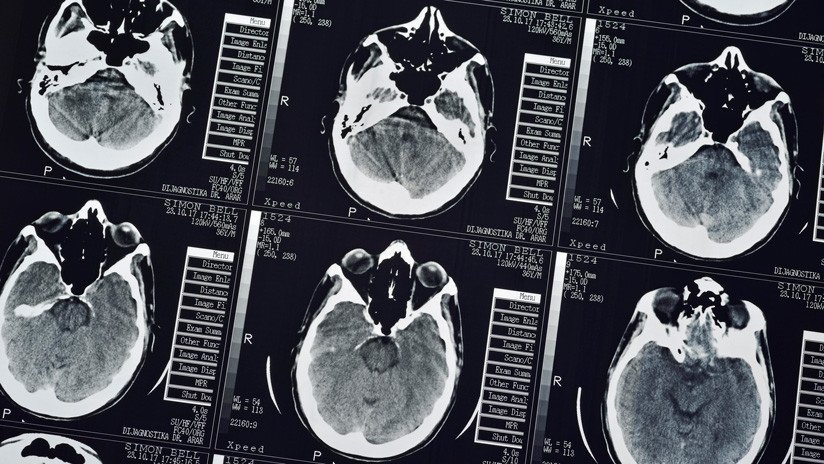

El médico encontró que más de 700 tenias, que el paciente albergó en su cerebro, pecho y pulmones, ya habían causado daños a sus órganos. "Hay múltiples presencias de lesiones que ocupan espacio en el cerebro del paciente. También están en los pulmones y llenan los músculos dentro de la cavidad torácica", señaló Wang.